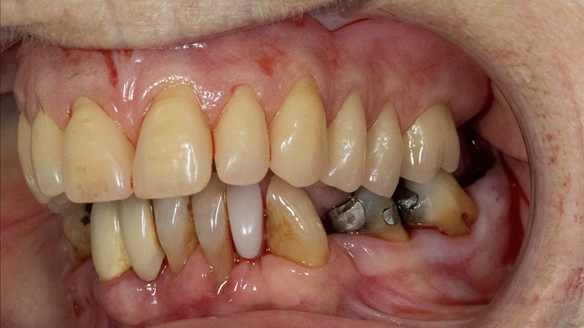

- The remaining natural upper natural teeth and lower back molars were heavily restored having generalised periodontitis stage 4 Grade C. Some of the teeth exhibited caries. The prognosis for these teeth ranged from dubious to hopeless.

- The upper and lower acrylic based partial dentures exhibited suboptimal extension of the flanges and saddles. They had poor retention, support, stability and tissue fit.

The clinical situation and treatment process is shown in detail below with photographs. In addition, threre is a link to the a 45 minute webinar I gave explaing this case. I provided the clinical work and Rowan Garstang provided the technical work.